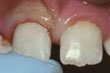

Αν χάσετε κάποιο δόντι από τραυματισμό, πάρτε το δόντι μαζί σας στον οδοντίατρο. Εάν είναι εφικτό να επανατοποθετηθεί το δόντι στο στόμα σας, η διαδικασία αυτή ονομάζεται επανεμφύτευση.

Εάν χάσετε κάποιο δόντι από τραυματισμό, το μυστικό για να επανατοποθετηθεί με επιτυχία στο στόμα σας, είναι να επανεμφυτευθεί στο φατνίο μέσα σε 30 λεπτά της ώρας και το αργότερο σε δύο ώρες. Κάθε λεπτό που περνάει νεκρώνονται κύτταρα της ρίζας. Ξεπλύνετε το δόντι μόνο με νερό, ακουμπείστε το στη θέση του και σπεύσετε στον οδοντίατρο, όσο πιό γρήγορα μπορείτε. Πρέπει να κρατάτε το δόντι από τη στεφάνη και να μην το αφήσετε να στεγνώσει. Μετά από μία ή δύο εβδομάδες και αφού το δόντι σταθεροποιηθεί, ο οδοντίατρός σας μπορεί να κάνει μια ενδοδοντική θεραπεία.

![]() | ξεριζωμένο δόντι |

![]() | επανατοποθετείστε προσεκτικά το ξεριζωμένο δόντι και πηγαίνετε αμέσως στον οδοντίατρό σας. |